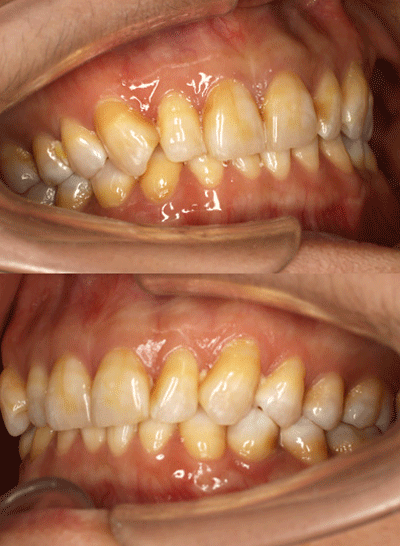

氟斑牙|瓷贴面修复——术前照片

术前侧面照